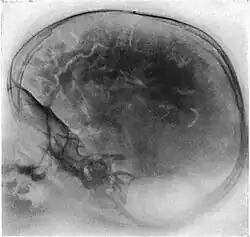

Neumoencefalografía

Una neumoencefalografía (a veces abreviada como PEG) era un procedimiento médico en el cual la mayor parte del fluido cerebroespinal es drenado de la cavidad craneana y reemplazado con aire, oxígeno o helio para permitir que las imágenes de rayos X muestren una mayor definición. Este procedimiento se deriva de la ventriculografía, un método más temprano y primitivo en el cual el aire era inyectado directamente a través de orificios practicados en el cráneo.